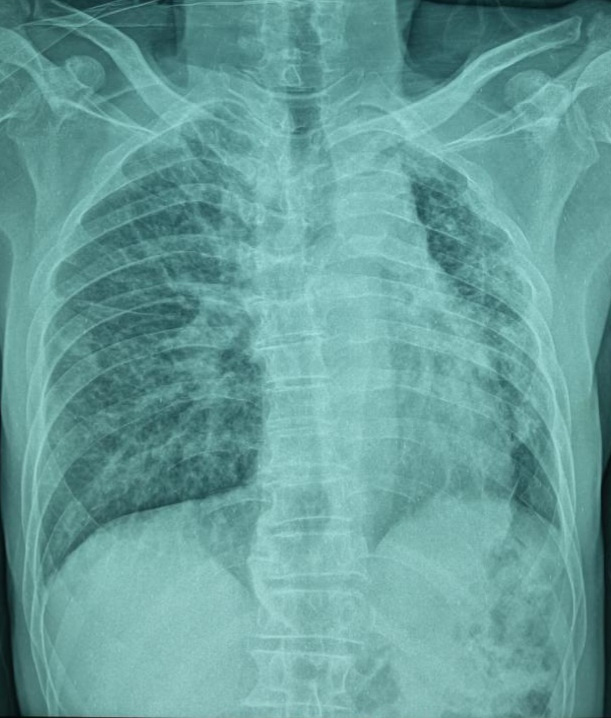

Un homme âgé de 66 ans, sans antécédents particuliers, est admis aux urgences pour la prise en charge d’un traumatisme thoracique minime. Une radiographie thoracique montre une asymétrie de taille des deux champs pulmonaires avec une déviation médiastinale vers la gauche (fig. 1). Un angioscanner thoracique montre une agénésie de l’artère pulmonaire gauche, une hypoplasie du poumon homolatéral et des lacérations vasculaires systémiques d’origine bronchique vascularisant le poumon gauche (fig. 2).